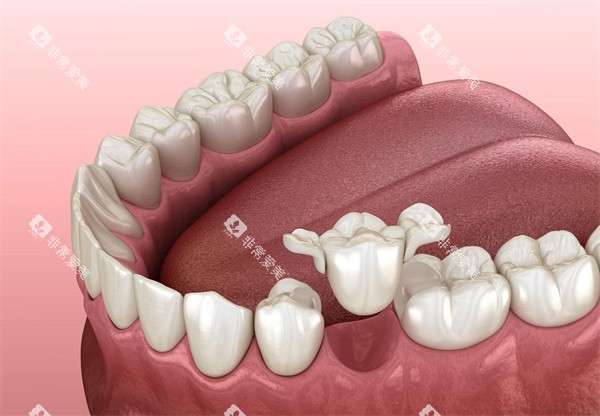

钴铬烤瓷牙:500元至1000元左右/颗。

纯钛烤瓷牙:1100元至2000元左右/颗。

国产爱尔创全瓷牙:1800元至3000元不等/颗,也有2400元起/颗的说法。

德国威兰德全瓷牙:4000元以上/颗,也有3600元至5000元/颗起的说法。

氧化锆全瓷牙冠:3000元至6000元起/颗。